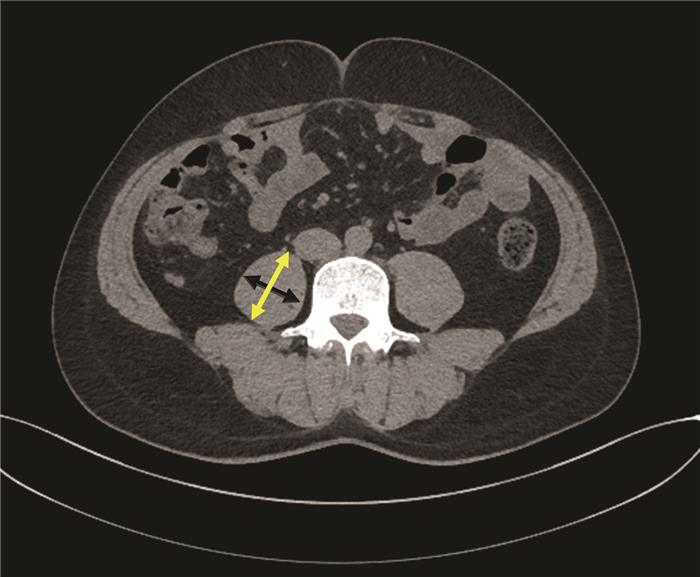

经正中裂联合左右侧入路完整切除肝尾状叶治疗小儿肝泡型包虫病1例报告

李汗, 侯立朝, 王海久, 王聪, 樊海宁

2022, 38(2): 426-429. DOI: 10.3969/j.issn.1001-5256.2022.02.033

摘要(1140) HTML (288) PDF (3527KB)(46)

摘要: